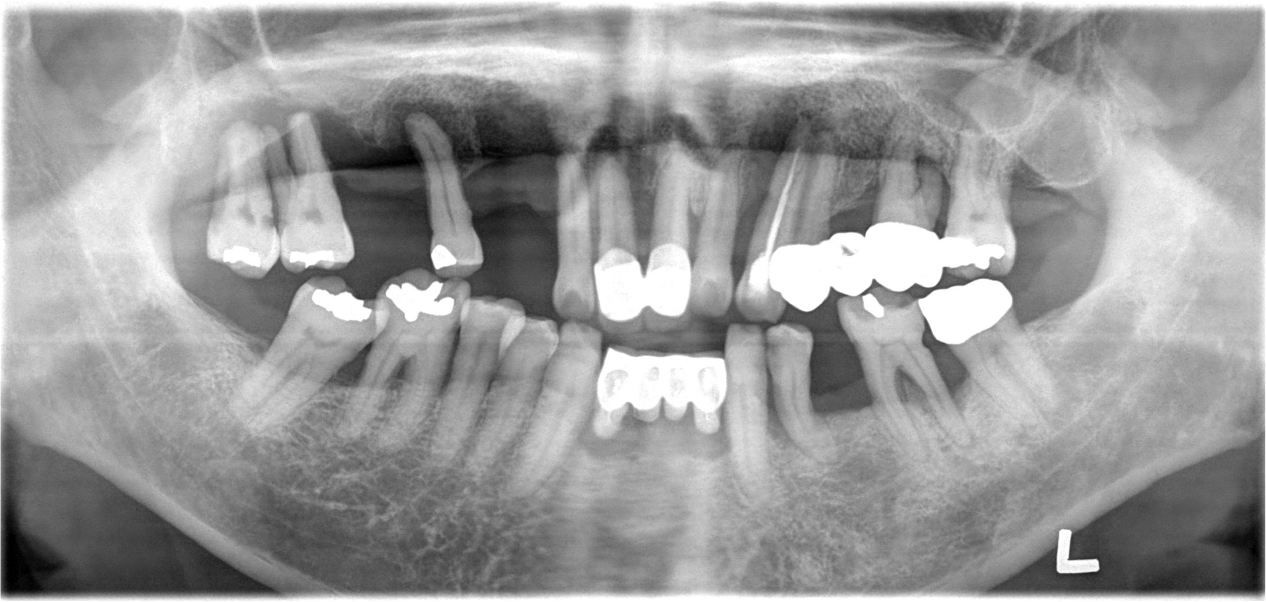

A 62-year-old male patient visited our clinic complaining of increased tooth mobility, gingival recession, and difficulty in mastication in October 2004 (Fig. 1). After clinical and radiographic examination, the maxillary and mandibular teeth with poor prognosis were extracted, and intensive periodontal treatment was performed on the remaining dentition. Through detailed prosthetic consultation with the patient, a conus double-crown-retained RPD using gold alloy for the inner and outer crowns was selected for the maxilla, while a fixed prosthetic denture was chosen for the mandible. The maxillary left lateral incisor, first premolar, first molar, and second molar were used as abutments for the conus double-crown denture. The prostheses were delivered in February 2005 (Fig. 2).